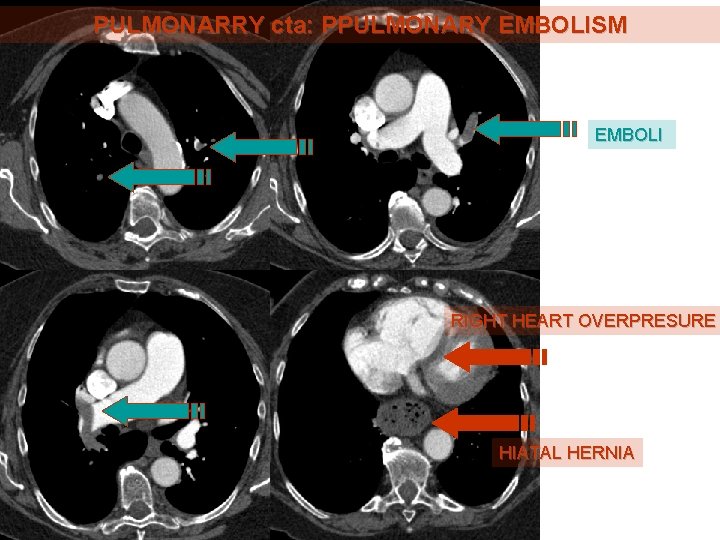

PULMONARRY cta: PPULMONARY EMBOLISM EMBOLI RIGHT HEART OVERPRESURE HIATAL HERNIA